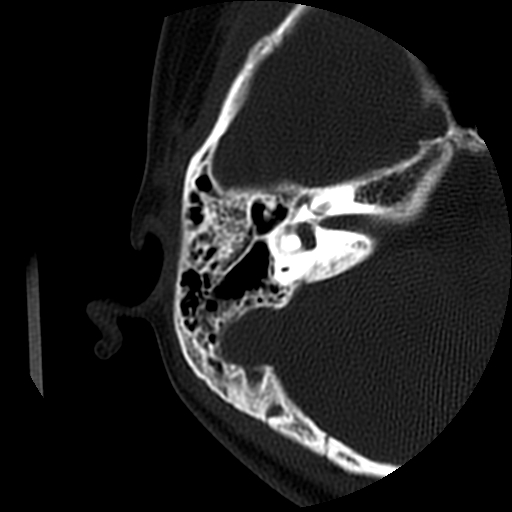

以下是引用随光逐影在2009-8-19 7:25:00的发言:[br]右侧慢性中耳乳突炎,右侧中耳腔及外耳道肉芽肿或胆脂瘤形成。